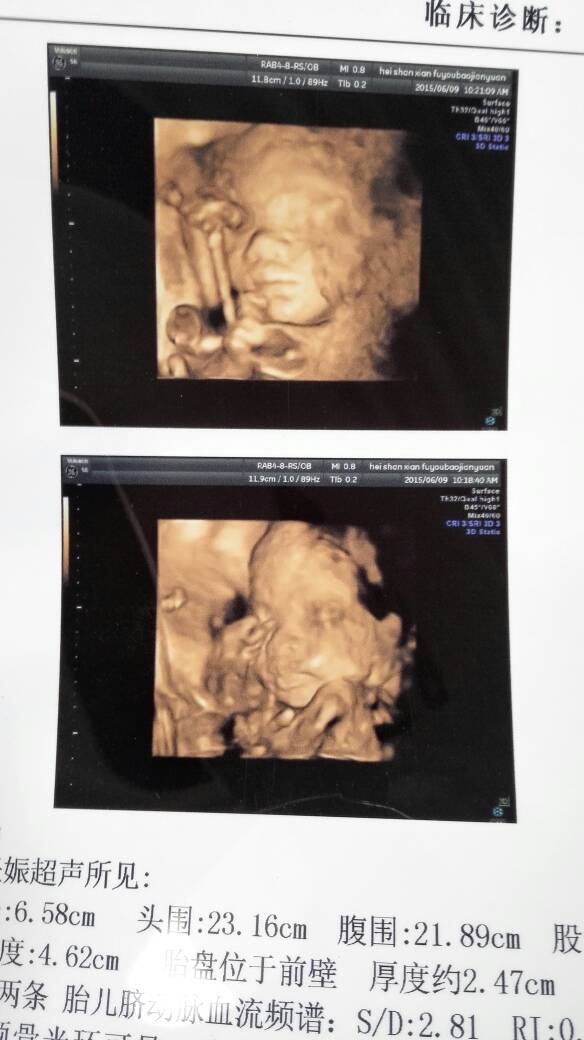

晒晒宝贝的四维照片,看着有点丑哈!!! 晒晒宝贝的四维照片,看着有点丑哈!!! 点击展开 ╭ 温唇°sunshine 2015-06-13 08:52 为您推荐: 其他回答 祝你好孕。 简💘爱💘 2015-06-13 10:25 ????? 183*****760_Cjy7 2015-06-13 10:13 没事!!! 诺言_BUkg 2015-06-13 09:48 都一样,,, 贺一诺 2015-06-13 09:23 你好,现在是看不出来宝宝丑、美的,其次只要检查胎儿发育一切健康的话,是没事的,另外建议 后面的孕期里还是需要做好定期产检的。观察胎儿的发育情况、羊水及胎盘的情况等。 shenglongxiao 2015-06-13 09:16 加载更多 相关问题 谁做过三维彩超的,晒晒你家的宝贝照片吧 可以晒未出生宝宝四维照片吗有什么说法 看看我家宝贝四维照片,是不是大眼睛高鼻梁的宝宝啊?